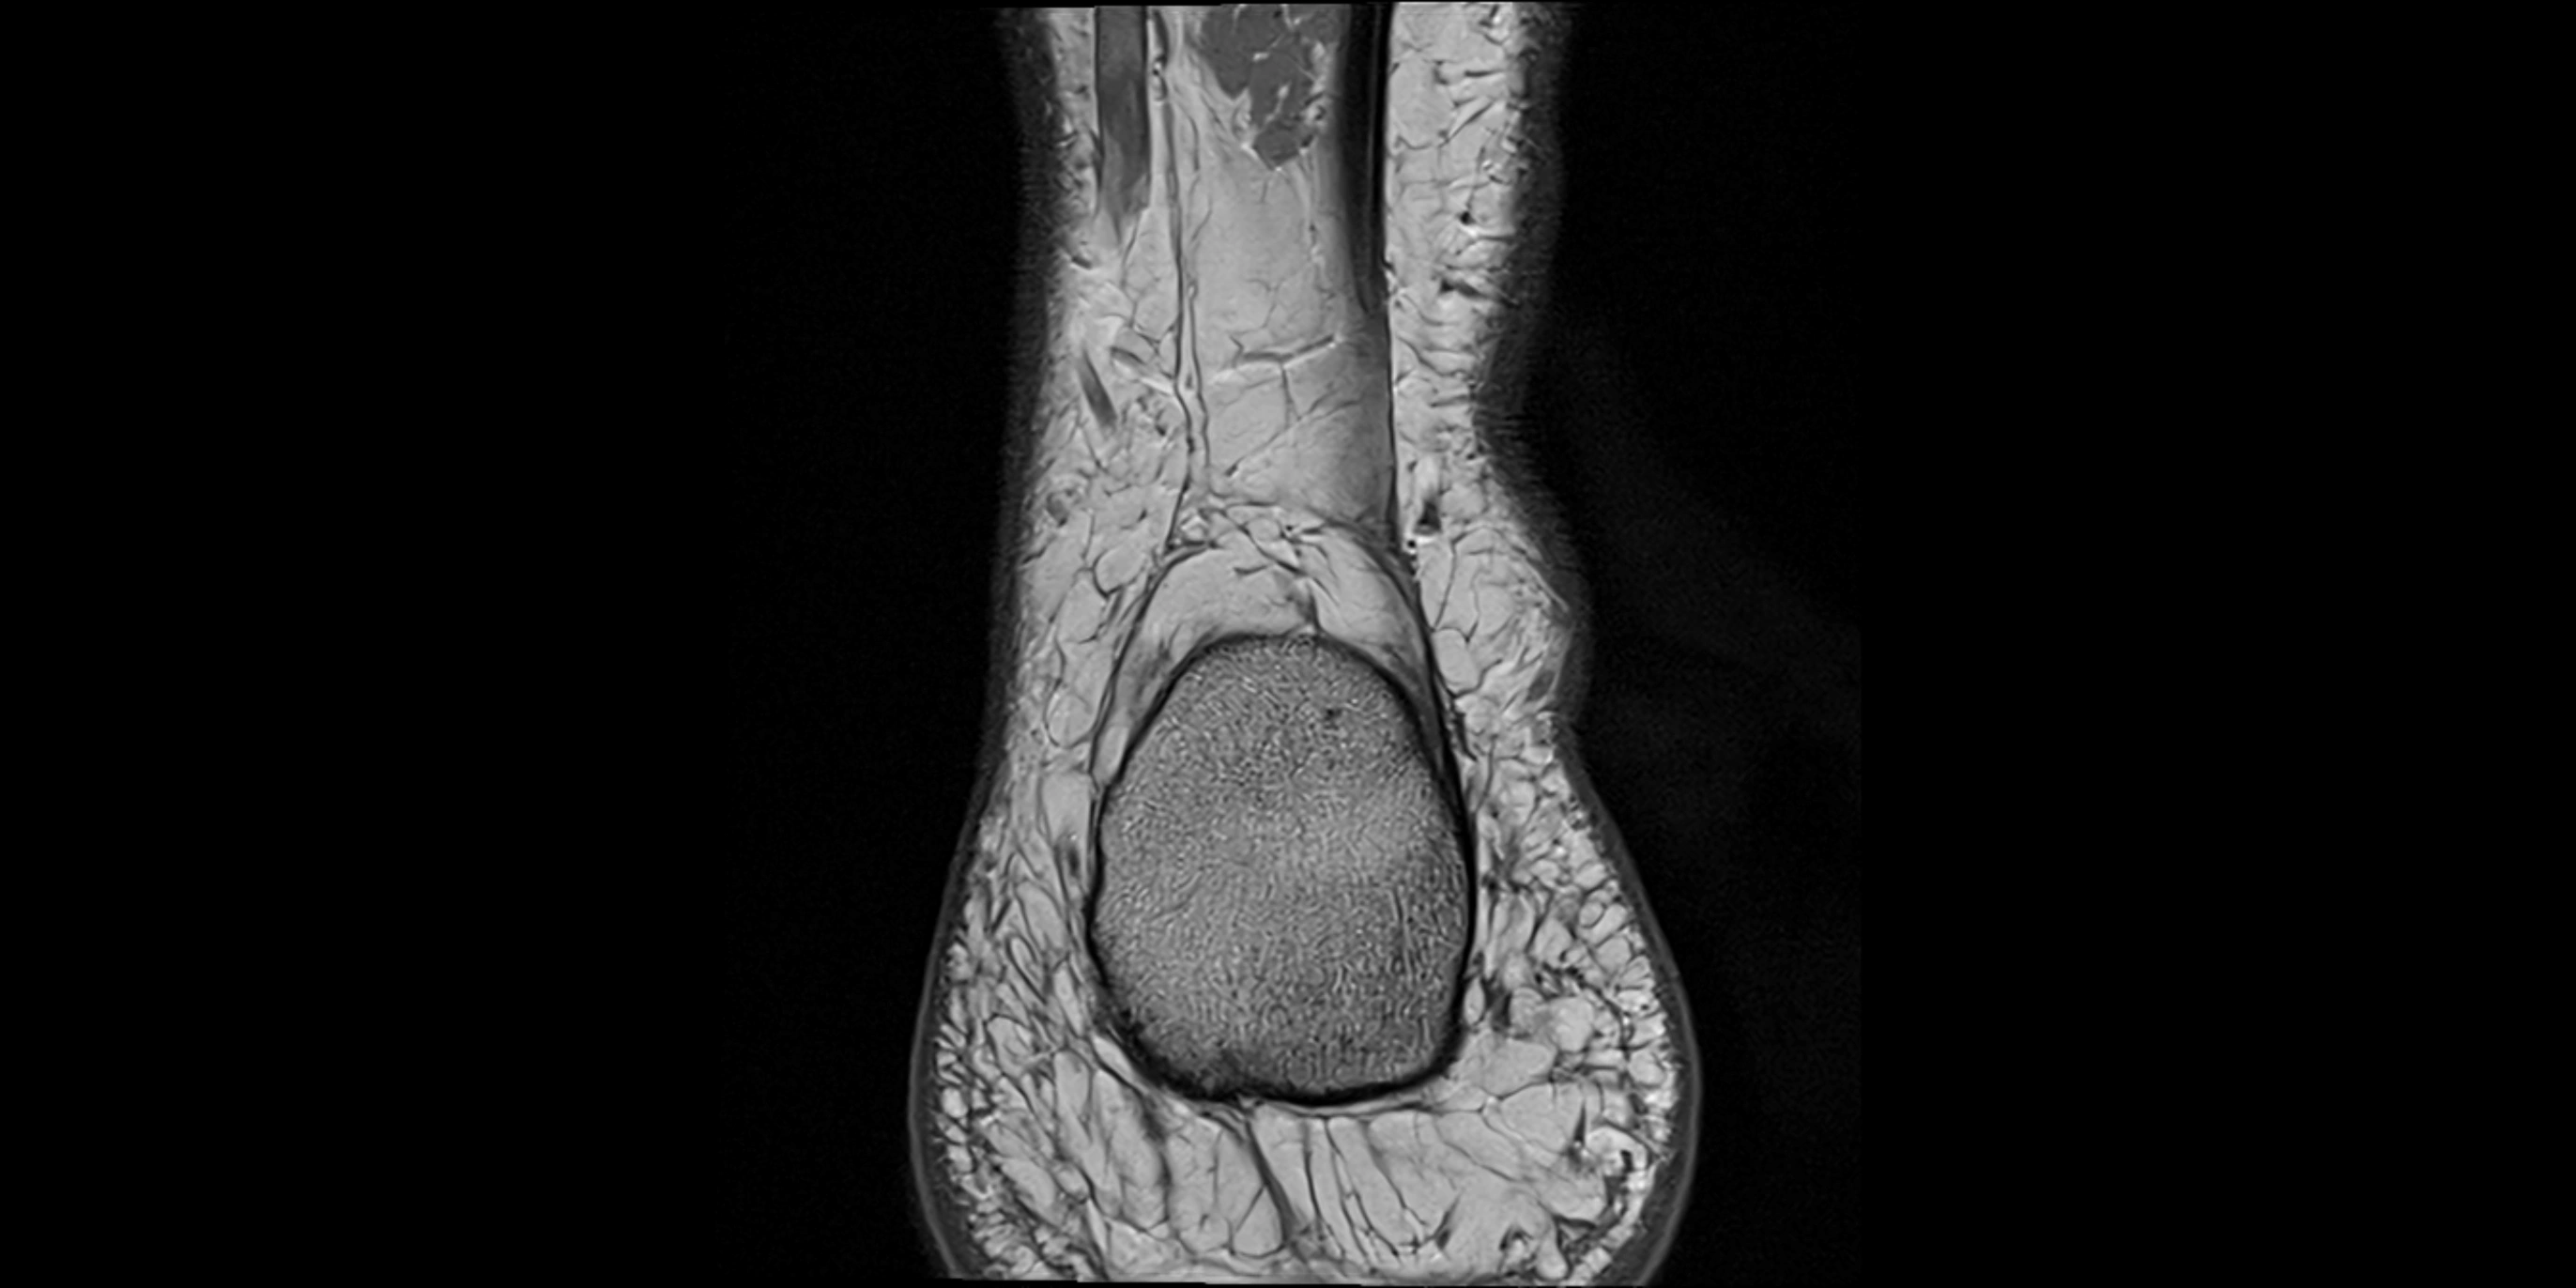

MRI image

image